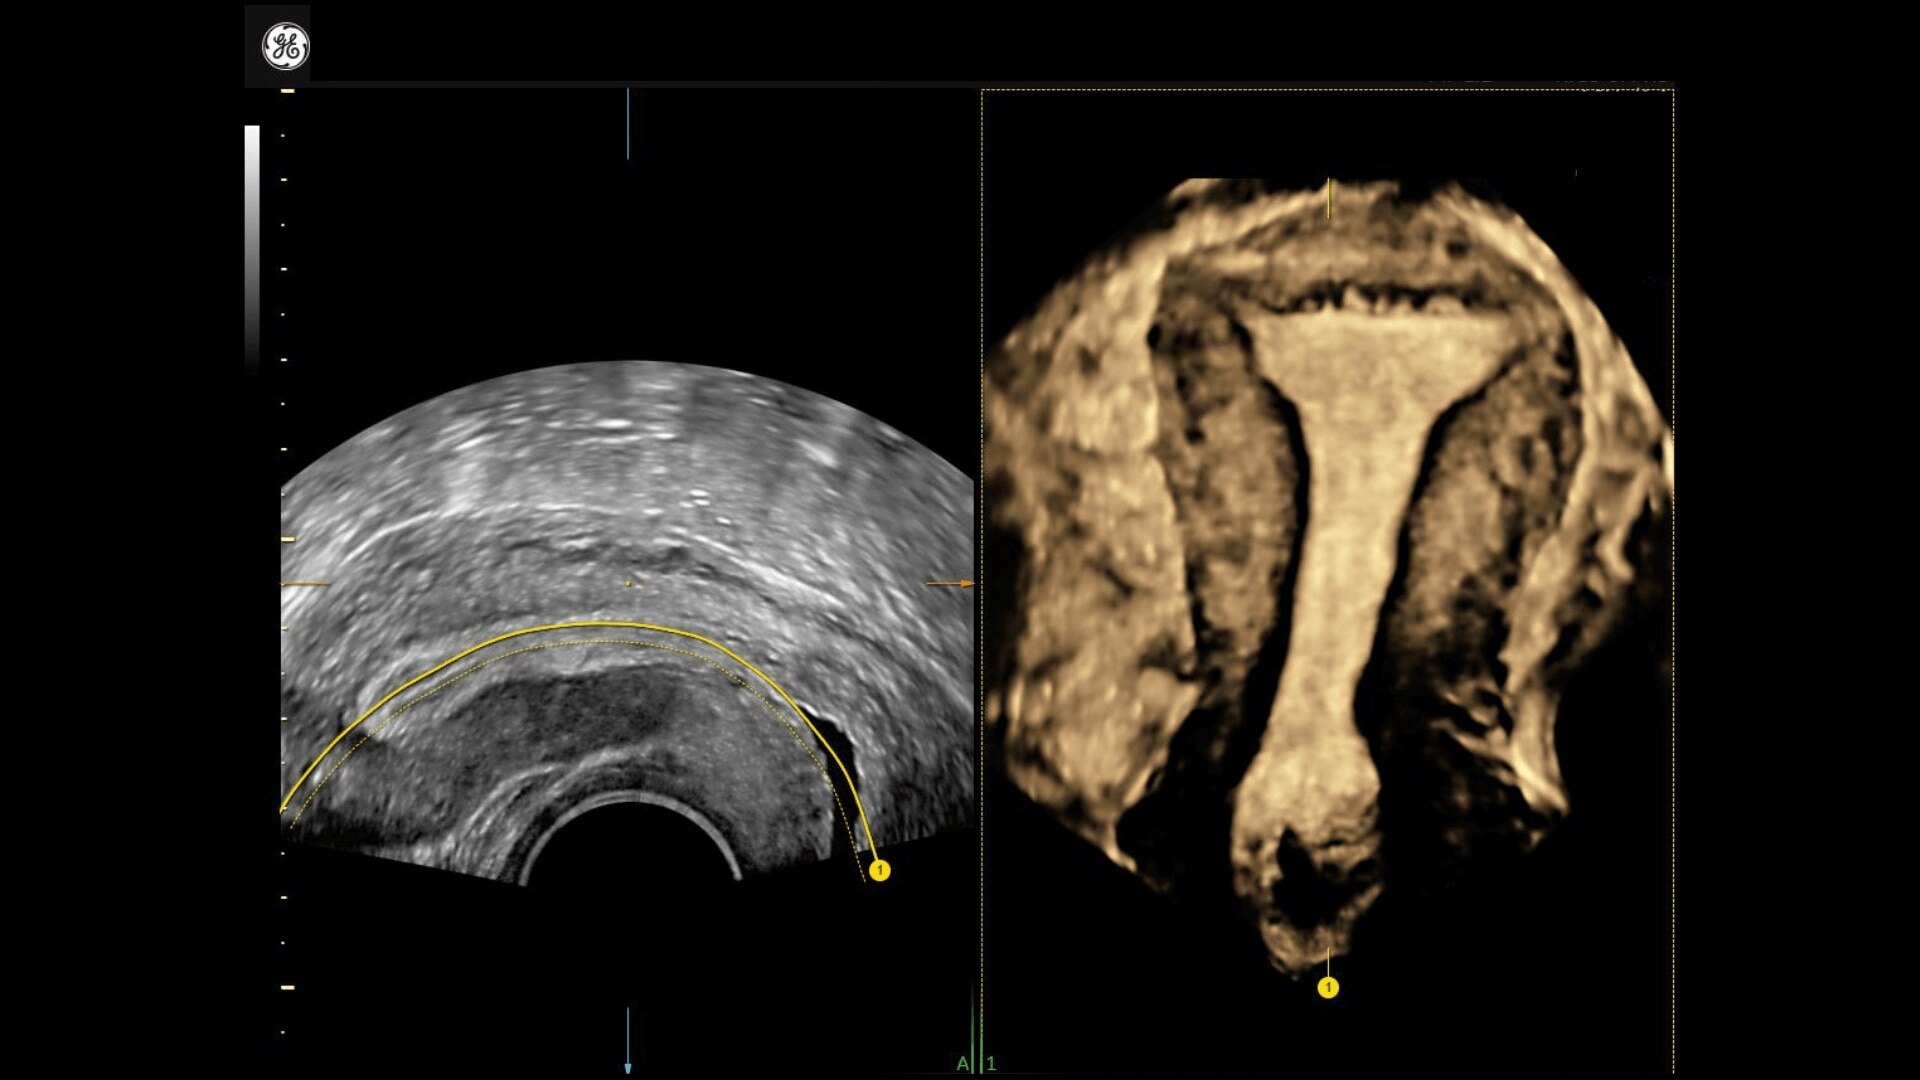

• Uterine Trace acquires the volume & then displays the coronal view of the uterus to simplify identification & reporting of uterine malformations.

• Adding 3D can provide more information to help inform your diagnosis and treatment plan. With a comprehensive set of 3D tools, you’ll have everything you need to easily obtain views not possible with standard 2D views.

• Uterine Trace acquires the volume and then displays the coronal view of the uterus linking to ASRM, ESHRE and ESGE Uterine Classification guidelines to simplify identification and reporting of uterine malformations